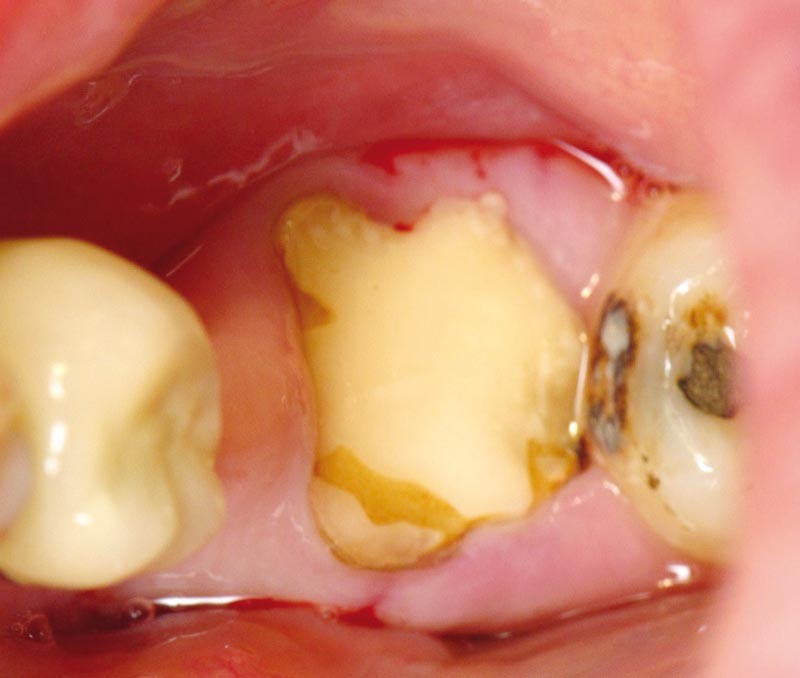

Pour avulser une molaire qui ne répond plus aux traitements conservateurs (fig. 1) et positionner un implant dans le même temps, nous devons résoudre les deux problématiques suivantes : extraire les racines en préservant le maximum de capital osseux et créer le lit implantaire sans détruire le septum inter-radiculaire.